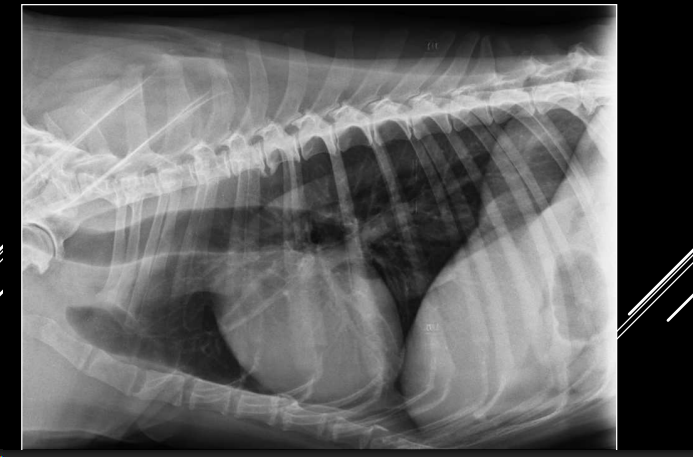

PULMONES

Parámetros técnicos:

- Proyecciones LL y VD.

- izquierdo 2 lobulos, derecho 4 de normal no se ve mucho. solo se ven los bronquios en patologías